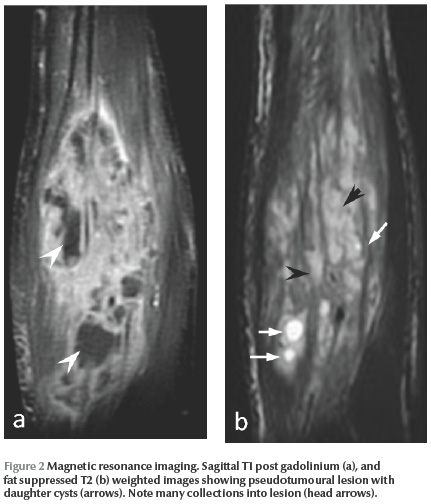

On physical examination, the mass was 14 × 7 × 6 cm, painful, warm and erythematous. Her fingers were retracted and Volkmann syndrome was suspected (Figure 1). US showed an echogenic solid and lobulated mass and a diagnosis of a tumour or abscess was made. MRI showed an impotent and heterogeneous soft tissue lesion with intermediate T1 and hyperintense T2 signals. T1 weighted images with fat suppressed and gadolinium injection demonstrated diffuse and considerable enhancement of the lesion suggestive of a tumour. T2 weighted images showed a low-density area in the lesion compatible with an abscess and fat suppressed T2 images showed 3 small cysts suggestive of hydatid disease (Figure 2 ). There were no bone abnormalities.

In our case, while US showed a pseudotumoural lesion and MRI showed an impotent lesion enhancement and abscesses, the presence of some small daughter cysts led to a diagnosis of hydatid cyst.

MRI is the imaging method of choice for the differential diagnosis. Rim sign and multicystic appearance are typical features of hydatid cyst [3,6]. The lesion usually has a high signal intensity on T2 and low intensity on T1 typically with daughter cysts. The rim sign, a low intensity rim on both T1 and T2, is not specific to hydatidosis and can also be seen in tumours with fibrous capsule. Pericystic enhancement can be seen and is often moderate [5] but in our case the enhancement was weak and diffuse because of the infection of the cyst. If the cyst is complicated, it is very important to search for daughter cysts, especially in fat suppressed T2 weighted images [4].